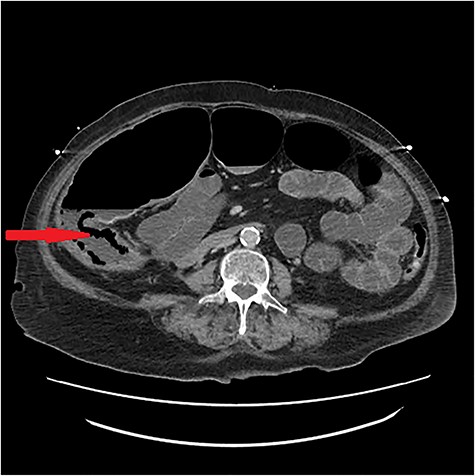

Lumbar puncture on admission was refused but done on Day 4 showing herpes simplex virus 1 infection and acyclovir commenced. On Day 13, an ultrasound for nonspecific abdominal pain showed cholelithiasis without cholecystitis and conservative treatment continued. Pain localized to the right iliac fossa over the next days; CT abdomen pelvis showed ischemia and pneumatosis (Figs. 1 and 2). The laparotomy on Day 18 confirmed bowel ischemia with retrocaecal perforation caused by a terminal ileal band that resulted in internal herniation and gangrene. An extended right hemicolectomy was done. As she was on the maximum dose of inotropes, the abdominal wall was kept open with a Bogota bag for re-look surgery in 24 hours. No progression of ischemia was noted subsequently and the stabilized patient had an ileostomy formed with closure of abdomen.

In our hospital, an arterial phase CT abdomen pelvis is gold standard and our patient’s scan showed acute bowel ischemia of the terminal ileum and ascending colon with pneumatosis (Figs. 1 and 2). The cause was suspected hypoperfusion due to the course of her illness and long intensive care unit stay but a mechanical cause was found on laparotomy, a terminal ileal band that precipitated internal herniation and subsequent compromise of bowel resulting in gangrene and retrocaecal perforation.